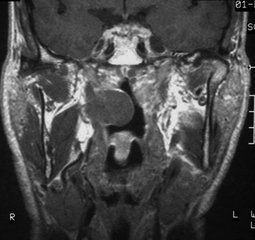

鼻咽血管纖維瘤鼻咽部血管纖維瘤疑難者應CT、MRI、DSA或99mTc2MIBI聯合檢查,特別是CT動態增強掃描和密度曲線的測定,以及MRI增強率的表達,對診斷或鑑別診斷有較大價值,結合病史,多能做出正確診斷。